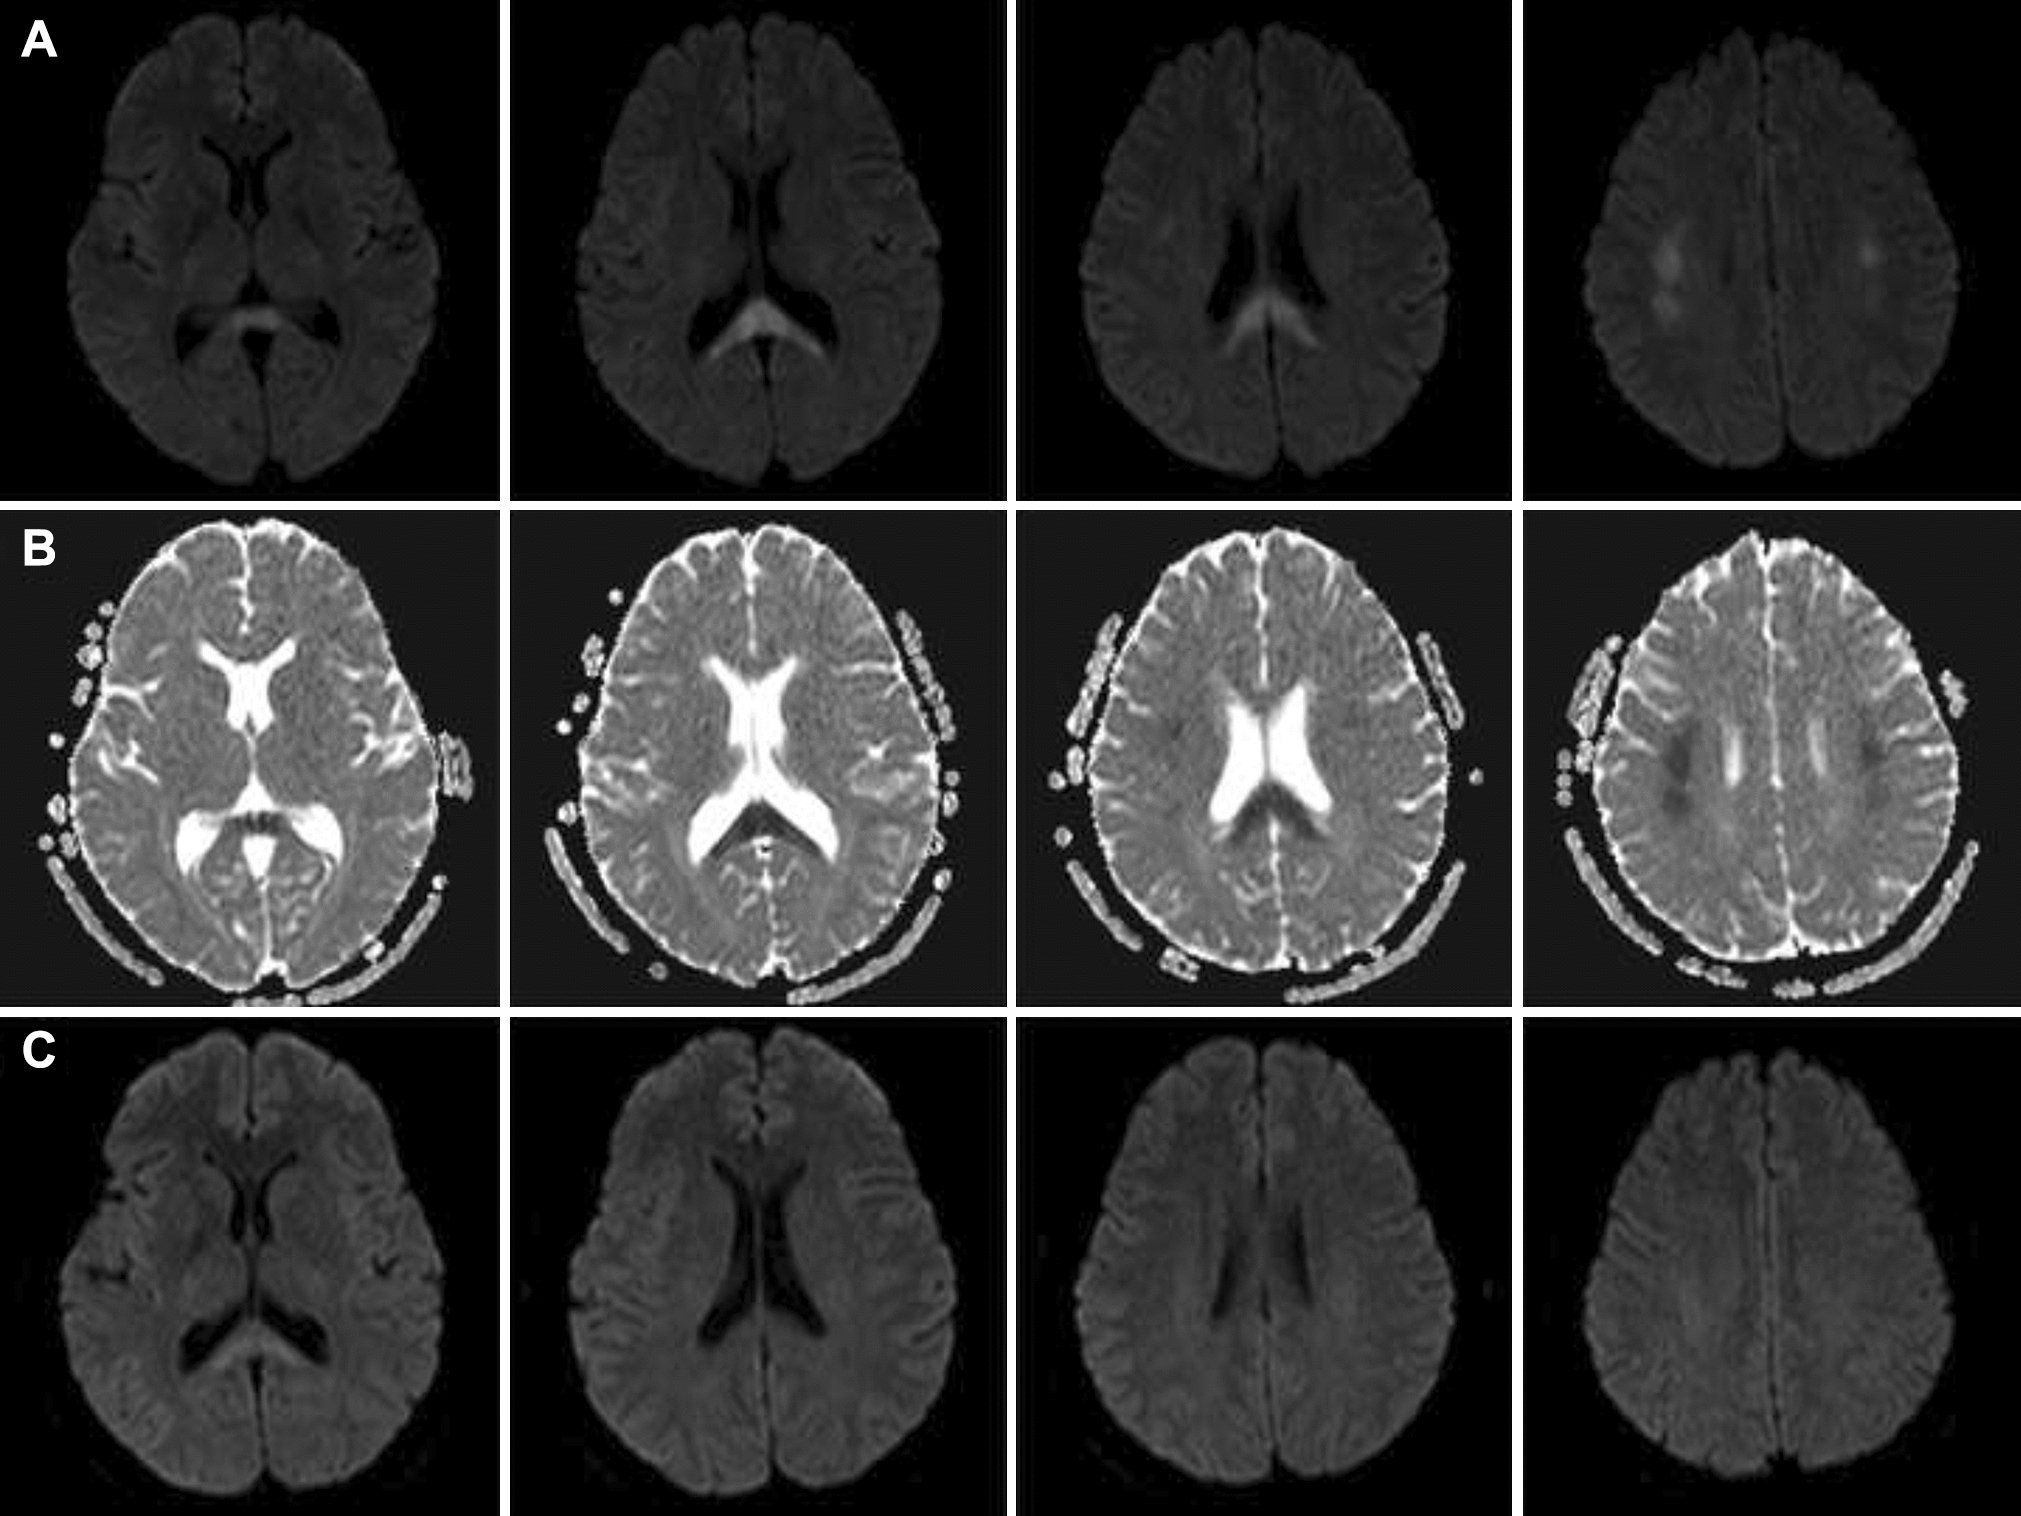

A 53-year-old woman was admitted with an altered state of consciousness for 8 hours. Two months earlier, she experienced slurred speech following a COVID-19 infection, but no remarkable abnormalities were found on pulmonary CT. Diffusion-weighted MRI revealed hyperintensities in the corpus callosum splenium and periventricular white matter with decreased signal intensity on apparent diffusion coefficient maps (Fig. 1A, B). After receiving symptomatic support and neuroprotective treatment, the aforementioned lesions significantly subsided (Fig. 1C), and the reverse transcription–polymerase chain reaction (RT–PCR) test for SARS-CoV-2 turned negative.

Fig. 1

Brain MRI two months before. Paired axial diffusion-weighted imaging and apparent diffusion coefficient map showed symmetric foci of restricted diffusion involving the corpus callosum splenium and periventricular white matter A, B. After 12 days of treatment, the above lesions significantly subsided C and the corresponding lesions largely disappeared on T2-weighted imaging and fluid-attenuated inversion recovery map (unshown)